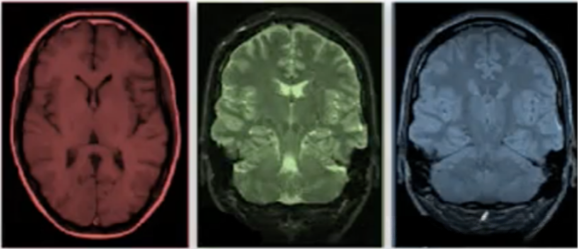

该项目旨在识别阿尔茨海默病(Alzheimer's Disease)患者的大脑头部3D MRI扫描图像中的三种类别:健康样本、轻度认知障碍样本和阿尔茨海默症样本。项目包含数据集准备、模型构建及训练等内容。

基于人体头部3D MRI扫描成像的数据集被划分为三个类别:分别为健康样本、轻度认知障碍样本以及阿尔茨海默症患者样本。研究团队通过利用该影像数据对模型算法进行训练,在独立测试集上尽可能提高分类准确性;每个样本均为三维体征的空间信息表示。

MRI 数据:每个 MRI sequence 包含大量切片构成的一个3D图像。该图像由长度、宽度以及切片数量构成。进而可知,单个的 MRI sequence 具备三个维度的信息:长度、宽度和厚度,因此可以作为一个三维张量。